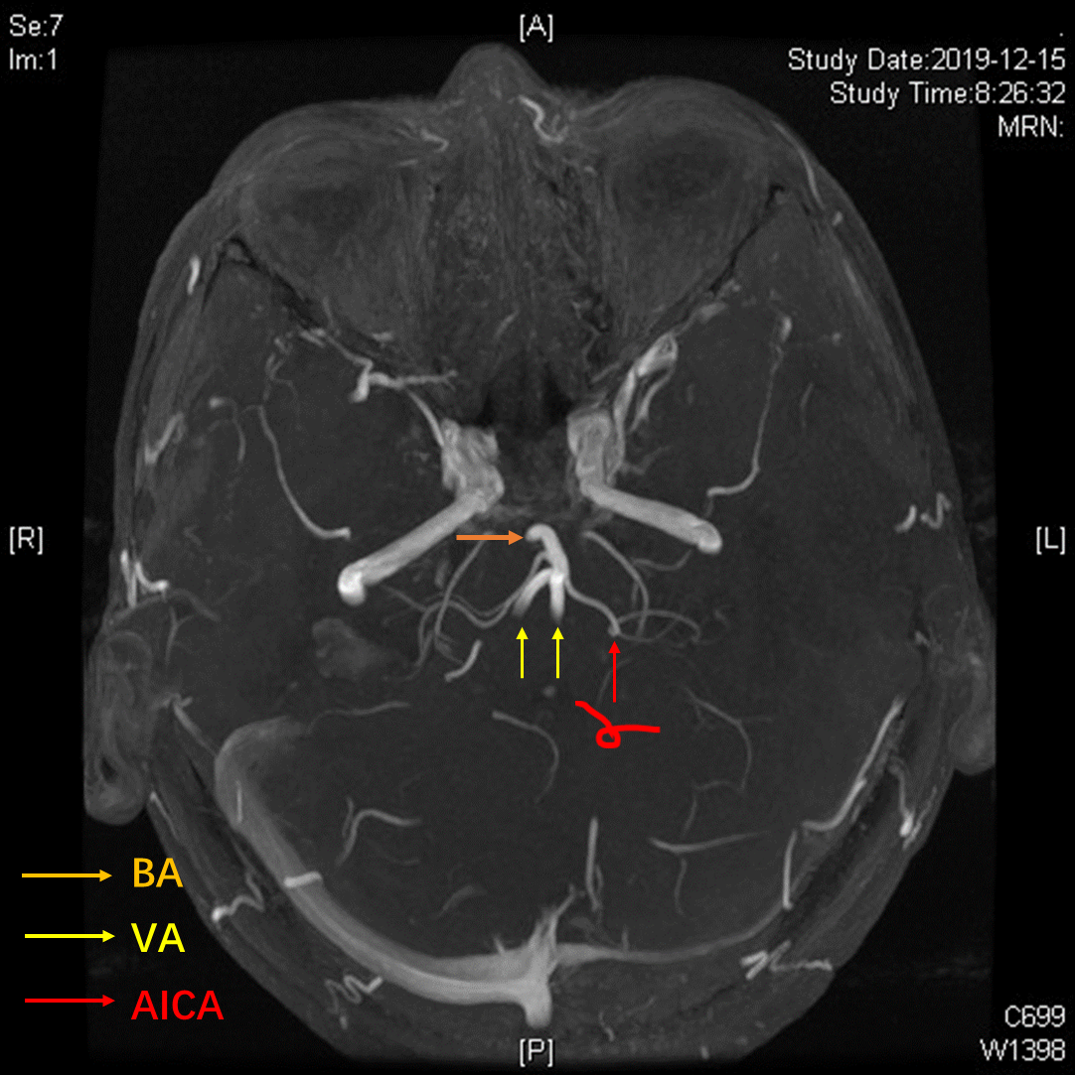

术前3D-TOF序列见左侧小脑前下动脉AICA从基底动脉发出,并弯曲成袢。

TOF序列及FIESTA序列见AICA向桥脑延髓沟方向弯曲,并与REZ区关系密切。

3D-TOF序列提示椎基底动脉迂曲,偏向右侧,小脑后下动脉PICA从劣势椎动脉发出,于上下各成一袢,最后绕回下方,呈“S”型。

TOF序列及FIESTA序列可见PICA在下方的第一个弯曲与面听神经关系密切。